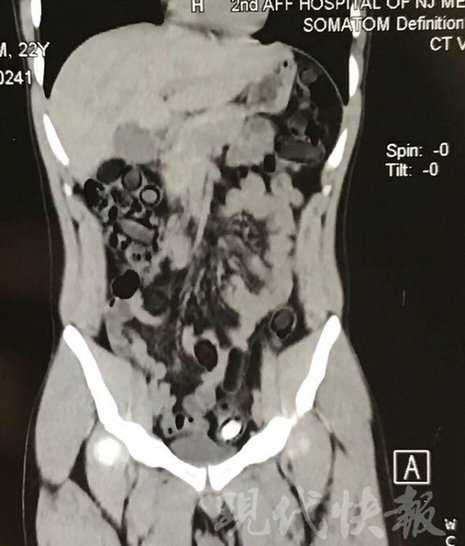

小伙體內(nèi)藏毒300余克 CT掃描圖密密麻麻

運(yùn)毒小伙:希望被判處死刑

由于毒品在體內(nèi)一旦泄露有可能致命,警方第一時(shí)間將阿永帶到醫(yī)院進(jìn)行檢查。CT 掃描的結(jié)果顯示,阿永體內(nèi)布滿(mǎn)了密密麻麻的白色圓柱狀固體,就像一粒粒的蠶蛹。在南京市公安局鼓樓分局二板橋派出所,阿永分四次排出了毒品,毛重369.99克。經(jīng)訊問(wèn),阿永交代了自己全部的犯罪事實(shí)。目前,阿永已被刑事拘留。